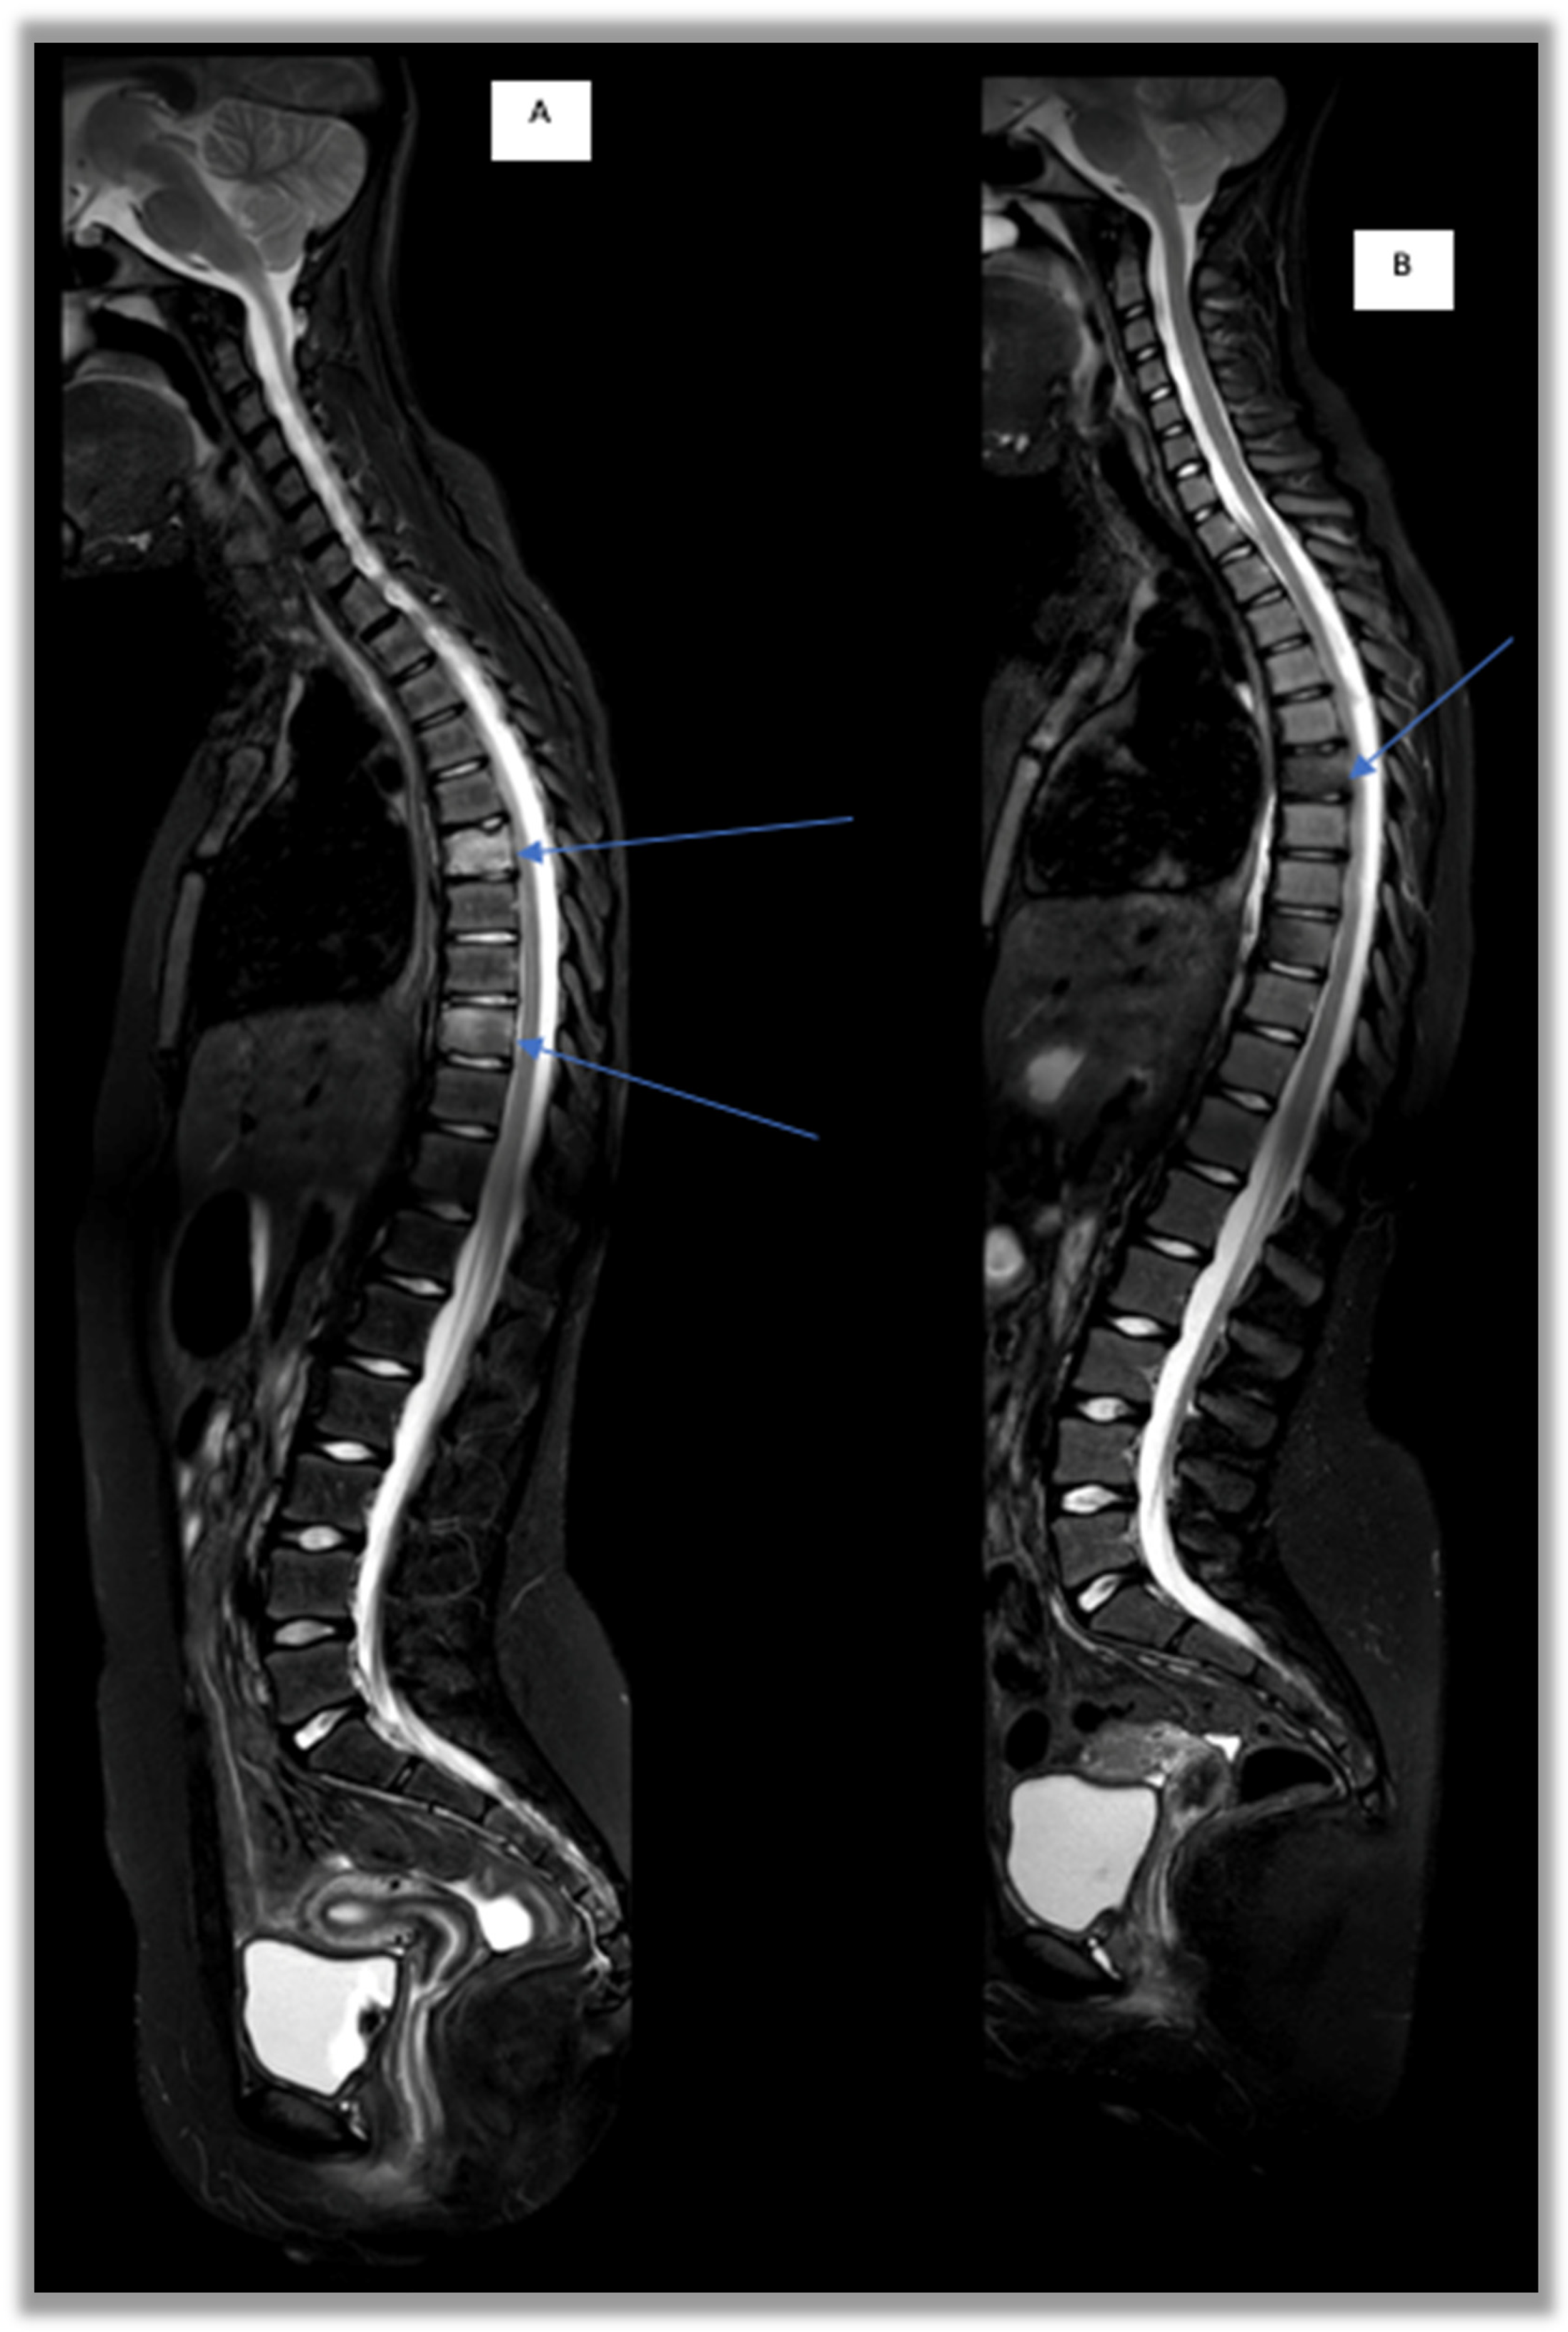

In several recent studies, an increase in the use of bisphosphonates is reported; these play an important role in bone remodeling by inhibiting osteoclastogene processes, reducing bone resorption and increasing bone mineralization [19,50]. In particular, given its rapidity of action, pamidronate is the most frequently used. More recent retrospective studies confirm the previous results, with remission achieved in 69.4–91% of patients [8,37,48,49,50,51,52] and in particular in cases of vertebral involvement [40,53] (Figure 5). More recently, a remarkably high response rate in vertebral lesions after pamidronate treatment has been shown, with 82.3% of lesions resolving completely, suggesting that pamidronate could be proposed as a first-line treatment in cases of spinal and mandibular involvement [50,52].

Figure 5.

STIR sagittal sequences of the spine. D6 and D9: vertebral involvement in a CNO patient before and after pamidronate treatment. (A) D6 and D9 vertebral edema, MRI-WB T0 pre-pamidronate; (B) regression of bone marrow edema at T12 follow-up post-pamidronate.